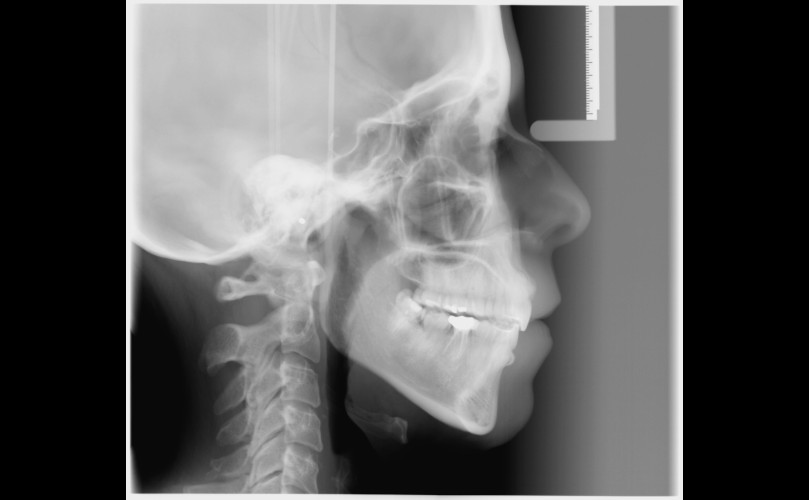

La importancia del perfil en el tratamiento de ortodoncia

Dentro de poco os enseñaremos las fotografías de este caso. Por ahora os dejamos con la radiografía lateral previa al tratamiento y la...